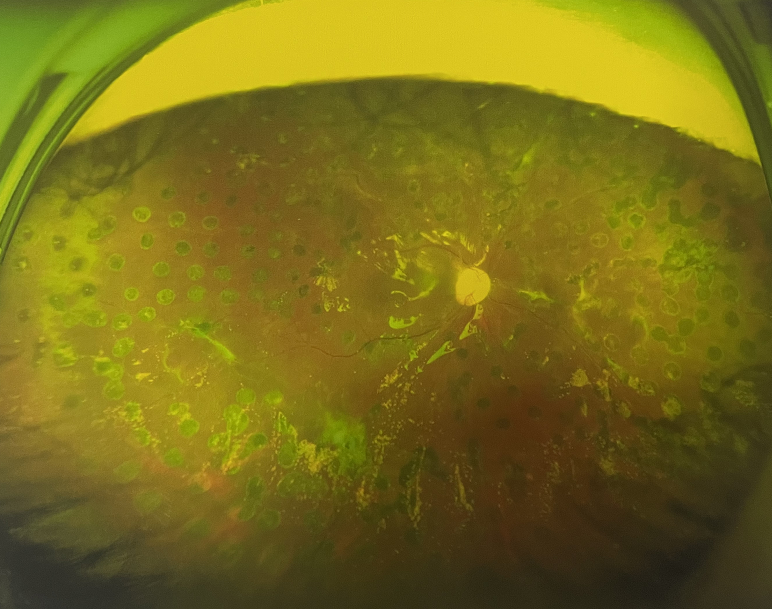

張小虎醫(yī)生為王女士進(jìn)行右眼玻璃體腔注藥術(shù),3天后進(jìn)行右眼23G玻璃體切割術(shù)后視力有所提升。

4個(gè)月后王女士來(lái)院取硅油,取油后視力恢復(fù)到0.6。“當(dāng)時(shí)來(lái)的時(shí)候真的只能看到模糊的影子,特別害怕覺得完了,想說(shuō)眼睛估計(jì)要瞎了,沒(méi)想到手術(shù)后視力竟然提升了,現(xiàn)在也看得比較清楚了。”王女士說(shuō)到。

張小虎醫(yī)生表示,糖網(wǎng)病進(jìn)展到嚴(yán)重增殖期帶來(lái)的視力損傷往往是極其嚴(yán)重的,目前王女士右眼從術(shù)前0.02恢復(fù)到術(shù)后0.6,已屬十分難得。

右眼術(shù)后